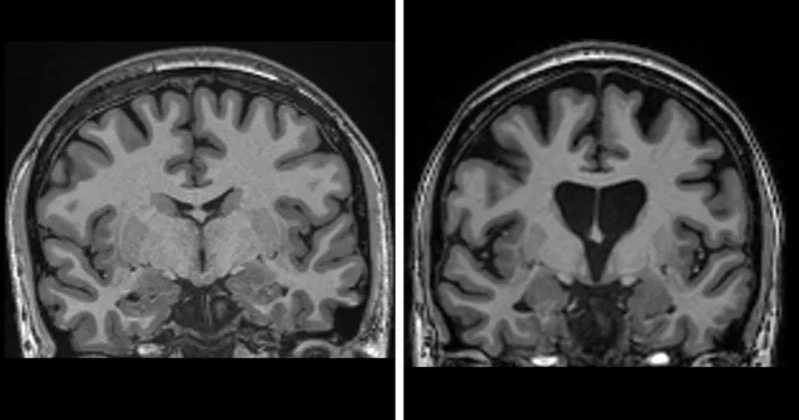

The disease, which destroys brain cells and combines symptoms of dementia, Parkinson’s, and motor neuron disease, has now been slowed by an average of 75% in a clinical trial. Experts say this could extend the decline normally seen in a year to four years, giving patients decades of improved quality of life.

The breakthrough involves an advanced gene therapy administered through 12 to 18 hours of delicate brain surgery. A harmless virus carrying specially designed DNA is infused into key brain regions using MRI-guided microcatheters. This prompts brain cells to produce microRNA, a fragment that silences the mutant huntingtin gene responsible for neuron death, lowering levels of the toxic protein in the brain, reports BBC.